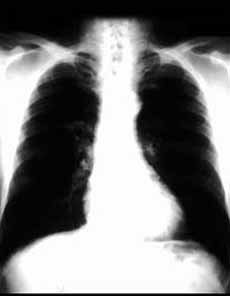

肺部X線表現為支氣管肺炎、非典型肺炎、胸膜炎和合併心血管病變4種類型。支氣管肺炎型:病變為沿支氣管分布於兩中、下肺野,密度不均勻,邊緣模糊的斑片狀炎症陰影、肺門影增寬。此型多見於兒童和老年患者;非典型肺炎型:支氣管周圍間質的片絮狀影,密度較淡,邊緣模糊,主要位於中、下肺野;胸膜炎型:呈胸腔積液徵象;合併心血管病變型:可有心力衰竭(急性肺水腫),心包積液的X線徵象。